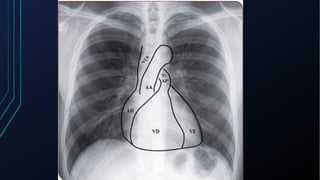

Projeção do Coração no Tórax

Noções de anatomia cardíaca

• Coração separado em 2 partes (direita e esquerda) e cada metade

consiste em 2 câmaras:

• Átrios -> Recebem sangue das veias

• Ventrículos -> Impulsionam o sangue para as artérias

• O átrio direito (recebe sangue venoso pelas veias cavas) -> Valva

tricúspide-> Ventrículo direito -> Valva pulmonar -> Artéria

pulmonar -> Pulmão -> Veias pulmonares -> Átrio esquerdo -> Valva

Mitral -> Ventrículo Esquerdo -> Valva aórtica -> Aorta